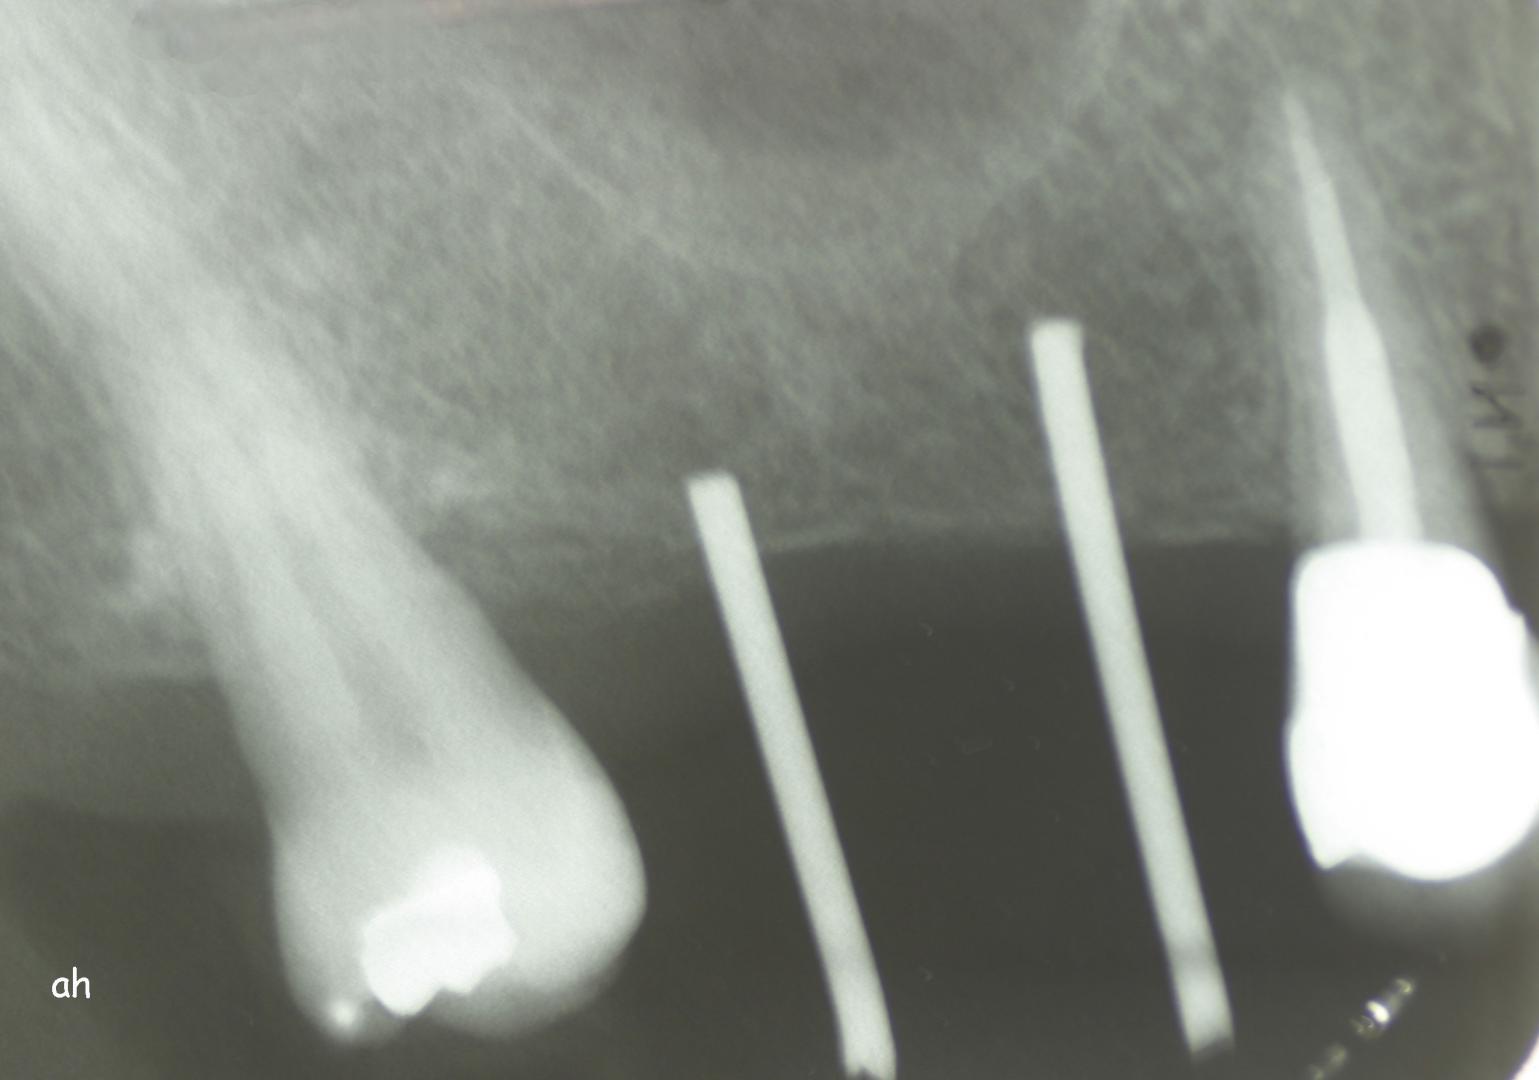

Exemple 12: Ici la pose de deux implants est envisagée, mais la hauteur d'os est insuffisante pour le deuxième implant. Le sinus (qui est une cavité creuse) est à moins de 6 mm de la surface de l'os. Idéalement il faudrait 10 mm d'os.

Exemple 12: Il faut donc relevé le sinus avec une greffe d'os avant de poser l'implant (Sinus lift).

Exemple 12: Les moignons vissés sur les implants 6 mois plus tard.

Exemple 12: Les couronnes en place.